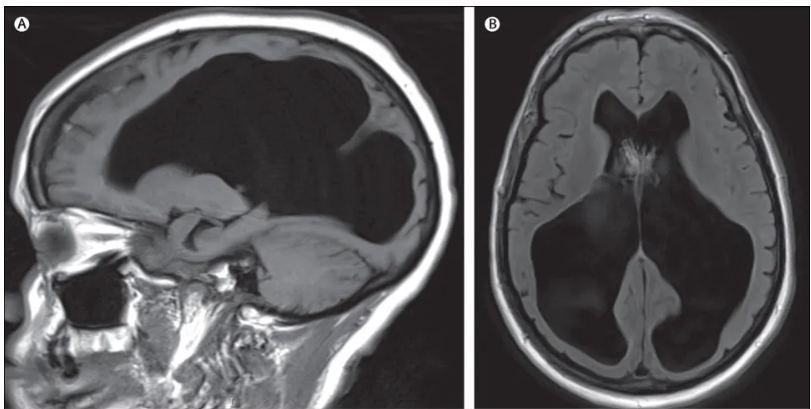

그의 뇌는 수 mm남짓의 막만 존재하고 내부는 뇌척수액으로 가득차 있었기 때문이다.

이는 뇌수종이라는 기존에 알려져 있는 병으로 그의 뇌는 거의 비어 있었다.

근데 문제는 그는 명문대생으로 셰필드대학교 수학과 재학생이었으며 그의 IQ는 126이었다는 것이다.